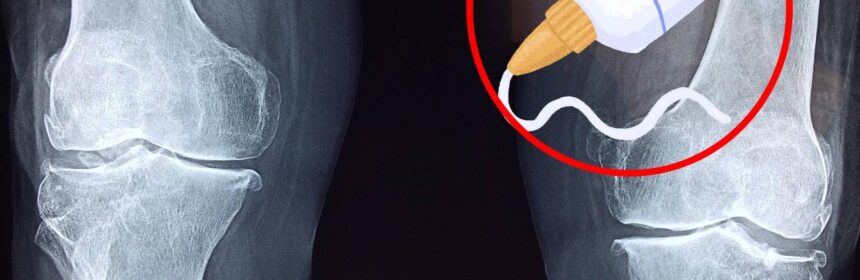

La aplicación y las propiedades de «Bone-02» prometen una transformación radical en la traumatología. A diferencia de las metodologías actuales, que dependen de la colocación mecánica de implantes, este adhesivo se aplica en el sitio de la fractura, logrando una fijación inmediata y resistente en el lapso asombroso de 180 segundos. Las pruebas preliminares han demostrado la robustez del material, indicando que los huesos tratados pueden soportar una fuerza de unión considerable, comparable e incluso superior a la resistencia de las técnicas tradicionales.